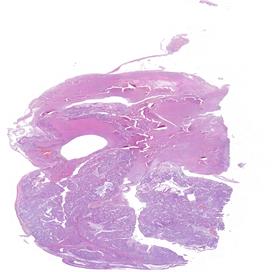

Il carcinoma sieroso ad alto grado dell’ovaio rappresenta una delle neoplasie ginecologiche più aggressive, con un alto tasso di recidiva e una sopravvivenza a lungo termine ancora limitata, nonostante i progressi terapeutici degli ultimi anni. I biomarcatori predittivi di risposta al trattamento, tra cui l’espressione del recettore dei folati (FRα), stanno emergendo come strumenti essenziali per personalizzare le terapie e migliorare gli esiti clinici delle pazienti. Il progetto nasce con l’intento di promuovere un apprendimento interattivo, coinvolgendo i partecipanti in attività mirate al miglioramento dei processi diagnostici e operativi. I patologi, infatti, rivestono un ruolo fondamentale nell’identificazione e caratterizzazione dei biomarcatori predittivi, contribuendo all’ottimizzazione dei percorsi terapeutici. L’evento, strutturato in due incontri online, si pone come obiettivo quello di fornire ai partecipanti gli strumenti teorici e pratici per l’esecuzione, la valutazione e l’interpretazione dei test di espressione dei biomarcatori. L’intento è quello di promuovere un approccio diagnostico sempre più integrato e personalizzato, ponendo l’accento sull’importanza di mantenere standard qualitativi elevati e monitorare nel tempo il proprio lavoro. Per raggiungere questo obiettivo formativo verranno messi a disposizione dei partecipanti kit specifici per esercitarsi nel perseguire la qualità e verificarla nel tempo. I risultati verranno poi discussi nella puntata finale del percorso.

OVAIO

2024 B 12863 A5 EE